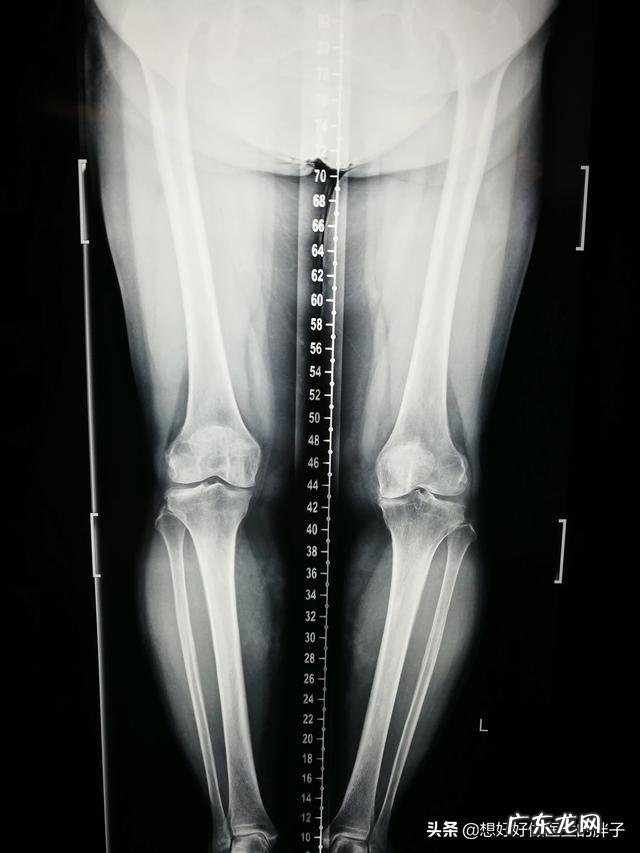

为什么会出现这种情况呢?主要的原因是由于我们所有人身体的承重力线主要经过的并不是膝关节的正中,都是偏内的 。

当人们进入老年阶段的时候,身体各方面都会表现出衰退,关节内的软骨也不再像年轻时那样充满弹性 。如果体重过大的话,一定会增加双膝关节承受的负担,最关键的是会增加膝关节内侧间隙承受的压力,所以很多体重较大的老年人在进入55岁左右以后,会表现出膝关节内侧的疼痛,不能正常蹲起,这都是由于关节内侧间隙受到了过度的压力导致的,严重的情况下会伴有内侧半月板的损伤 。